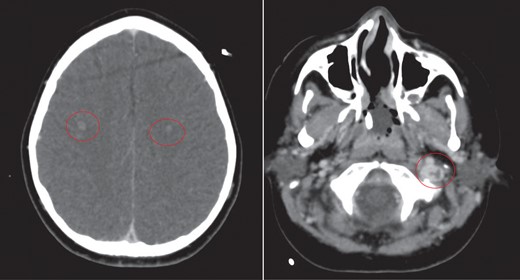

CT of the head with contrast revealed opacification of the left mastoid air cells with multiple ring enhancing abscesses throughout the brain, the largest of which in the left cerebellar hemisphere, measuring 4.4 × 2.9 cm in maximal axial dimensions (Fig. 6). There was non occlusive thrombus of the left internal jugular vein and superior sagittal sinus (Fig. 7). A repeat CT thorax revealed persisting left lung abscesses, a left sided collection and a new post drainage large, right-sided haemothorax.

CT scan of head with contrast revealed multiple ring enhancing lesions within the brain, opacification of the left mastoid air cells and thrombus within the superior sagittal sinus and left internal jugular vein.